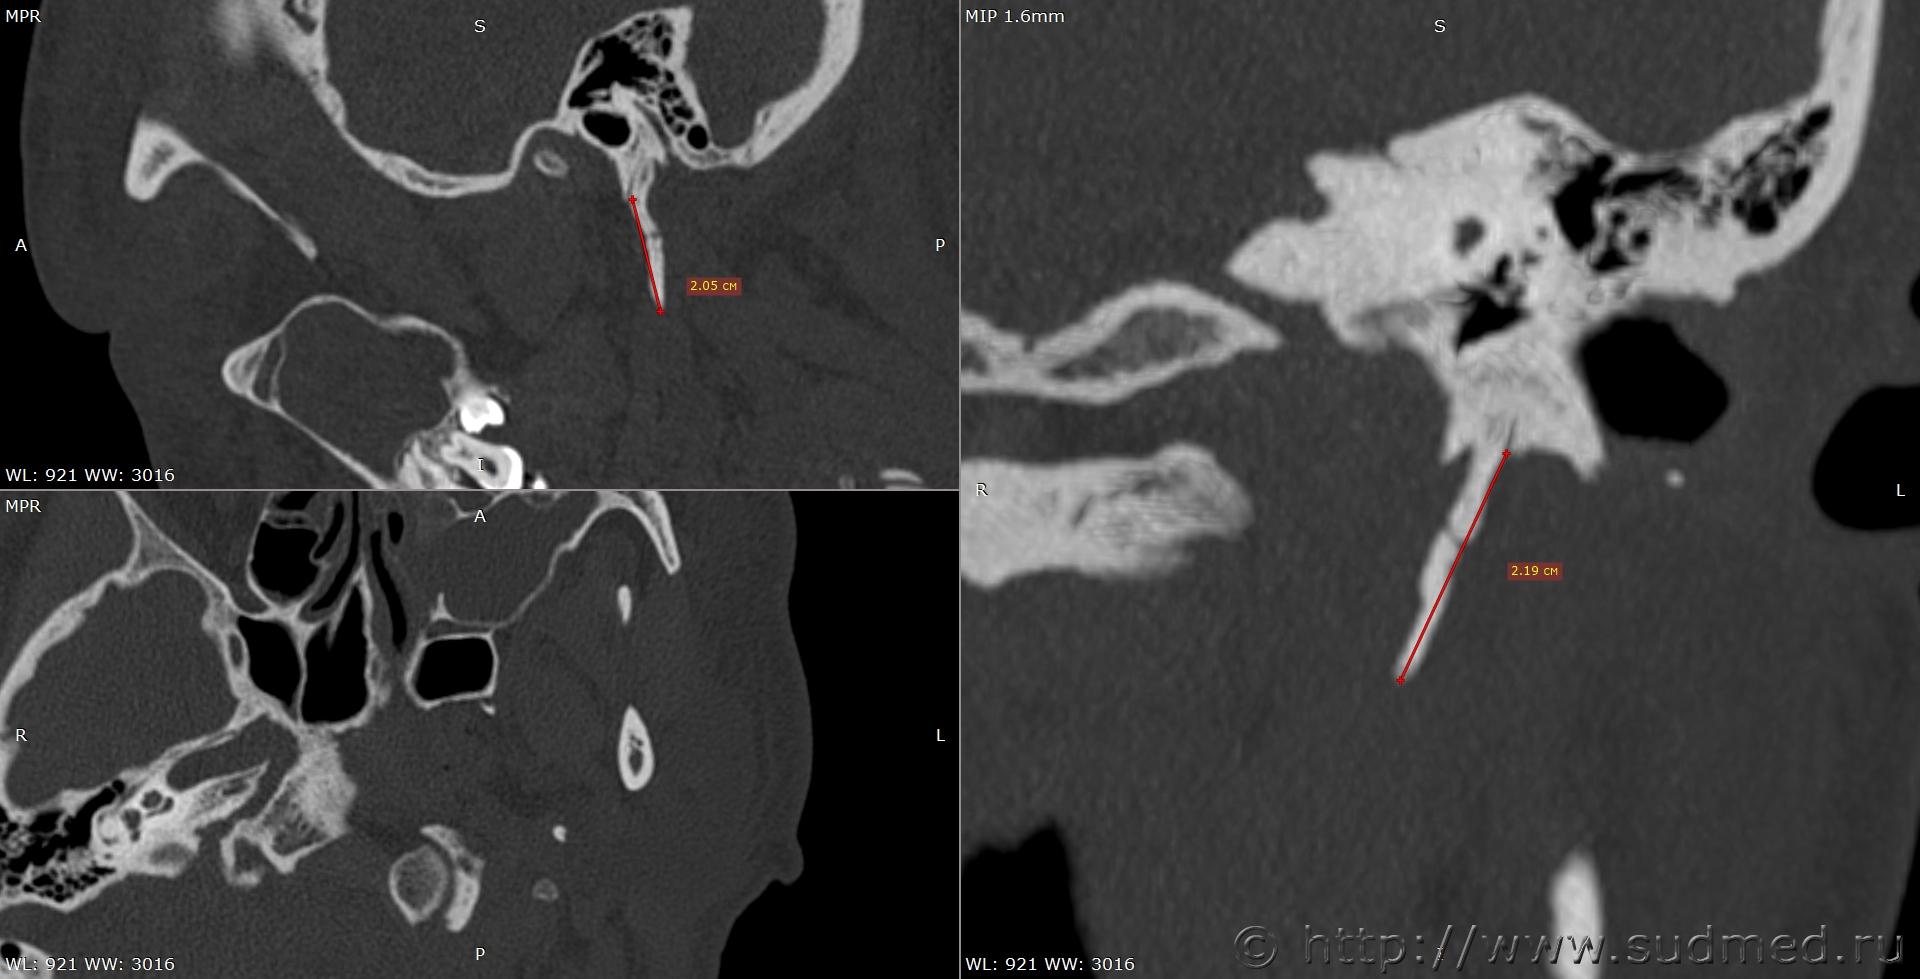

При экспертизе живого лица по медицинским документам встретились переломы шиловидных отростков височных костей. Женщина 39 лет, обратилась за медицинской помощью на 5-е сутки после травмы, тогда же провели РКТ. До этого никуда не обращалась. В протоколе РКТ отметили перелом шиловидного отростка левой височной кости, на снимках перелом на границе верхней и средней трети, дистальный отломок слегка смещен кпереди, каких-либо признаков заживления нет. Длина отростка 2,19 см. Судебная медицина - Прикрепленное изображение Также на КТ визуализируется перелом шиловидного отростка правой височной кости в нижней трети с выраженным смещением, думаю, отрывного характера (его длина 2,01 см), также без каких-либо признаков заживления Судебная медицина - Прикрепленное изображение; и гематома теменной области слева с переходом, в частности, на левую височную область, область левого сосцевидного отростка, левые околоушно-жевательную и скуловую области, левую боковую поверхность шеи Судебная медицина - Прикрепленное изображение, увеличение в объеме, нечеткость контура и разволокнение левой грудино-ключично-сосцевидной мышцы и левой ременной мышцы головы в верхней трети Судебная медицина - Прикрепленное изображение, вокруг них, в том числе кнутри от ременной мышцы, повышение плотности ПЖК Судебная медицина - Прикрепленное изображение; такие же изменения плюс повышение плотности левой подкожной мышцы шеи Судебная медицина - Прикрепленное изображение, увеличение в объеме и нечеткость контура левой околоушной слюнной железы, левая жевательная мышца не изменена Судебная медицина - Прикрепленное изображение. У подъязычной кости вижу нарушения целостности левого большого рога, но окостенение не завершено, края четко не визуализируются, поэтому о характере нарушений целостности не могу судить. Судебная медицина - Прикрепленное изображение Судебная медицина - Прикрепленное изображение В осмотрах врачей какие-либо изменения в области шеи, изменения голоса, соответствующие жалобы не отмечены; на 6-е сутки выставили острый фарингит. Помимо этой травмы есть переломы костей носа, там ничего особенного.